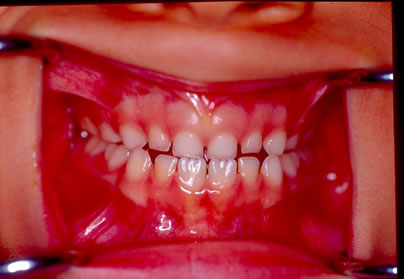

I° Caso- La piccola S.T. di anni 4 è giunta alla nostra osservazione per una visita ortodontica mandata dal suo pediatra di famiglia. All'anamnesi risultava che la bambina respirava prevalentemente con la bocca e durante la notte russava e andava i apnea. All'esame clinico ortodontico la bambina presentava un morso inverso anteriore con palato ogivale (Figura 1).E' stato richiesto quindi un monitoraggio cardio-respiratorio che è stato eseguito con un poly-mesam 8 canali portatile. Tale esame ha evidenziato un RDI =13 associato a forte russamento (Figura 2). Sulla radiografia del cranio in proiezione latero-laterale è stata eseguita l'analisi cefalometrica che ha messo in evidenza una I classe scheletrica con tendenza alla III in soggetto ipodivergente. In considerazione del morso inverso e del palato ogivale, si è deciso di applicare un espansore rapido palatale con ganci per maschera di Del aire (Figura 3). Ottenuta l'apertura della sutura palatina è stata applicata la Maschera facciale di Delaire per la trazione postero-anteriore del mascellare superiore. Dopo 2 mesi dall'inizio della terapia è stato eseguito un monitoraggio cardio-respiratorio di controllo che ha messo in evidenza un RDI= 5 con riduzione del russamento rumoroso (Figura 4). Dopo 6 mesi, ottenuta la correzione del morso inverso e del palato ogivale, una volta rimosso l'espansore rapido e la maschera facciale, è stato applicato un apparecchio funzionale di III classe come mantenimento. La correzione della malocclusione ha coinciso con il miglioramento dei sintomi respiratori come anche riferito dalla madre.